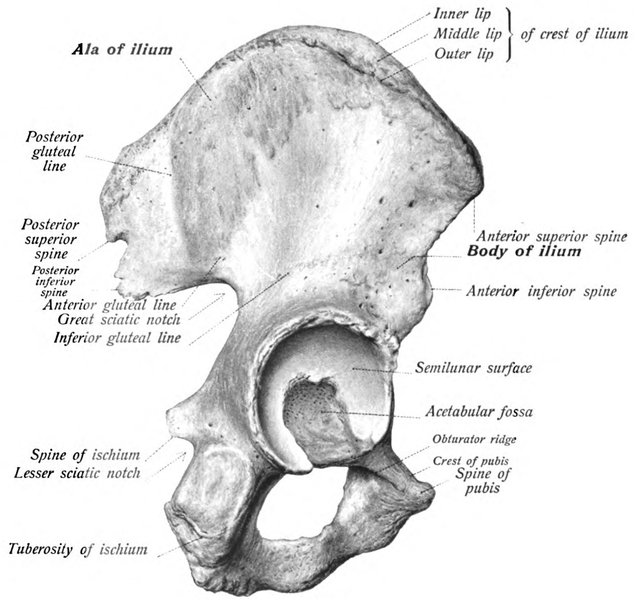

Asas Ilíacas (ao alas): Parte do osso pélvico.

| Vista lateral do osso ilíaco (osso pélvico) mostrando a asa ilíaca. Imagem de: Dr. Johannes Sobotta publicado na Wikipedia. |